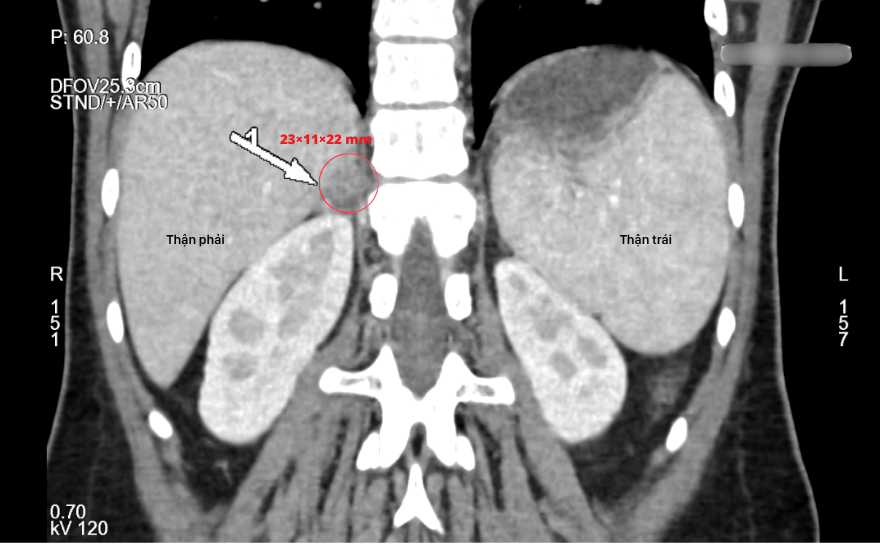

The patient subsequently underwent abdominal computed tomography to localize the lesion. Imaging revealed a right adrenal mass measuring approximately 23 × 11 × 22 mm, with features consistent with a benign adrenal adenoma.

Based on the combined clinical, biochemical, and imaging findings, the patient was diagnosed with Conn syndrome secondary to a right adrenal adenoma.

Computed tomography imaging demonstrated a right adrenal mass measuring approximately 23 × 11 × 22 mm.